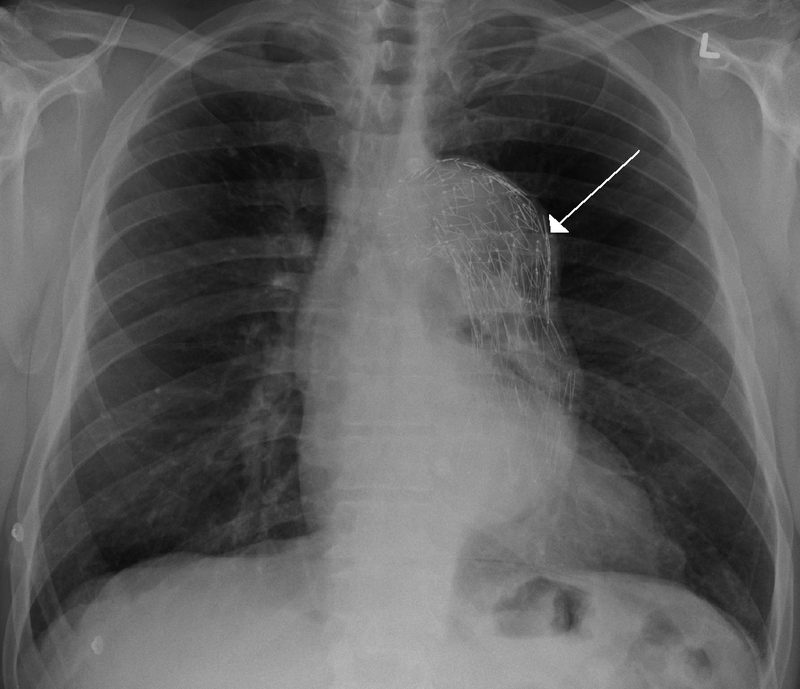

Thoracic Aneurysm

An aneurism of the thoracic aorta is a thoracic aneurysm.

Thoracic aneurysm risk factors include:

- Syphilis

- Hypertension

Tertiary syphilis is a common cause of thoracic aneurysm.

Tertiary syphilis can cause vasa vasorum endarteritis leading to thoracic aneurysm due to:

- Luminal constriction

- Reduced blood flow

- Vascular wall atrophy

Tertiary syphilis results in the aorta having a “tree-bark” look.

Complications of thoracic aneurysm includes:

- Airway compression

- Esophagus compression

- Thrombosis

- Embolism